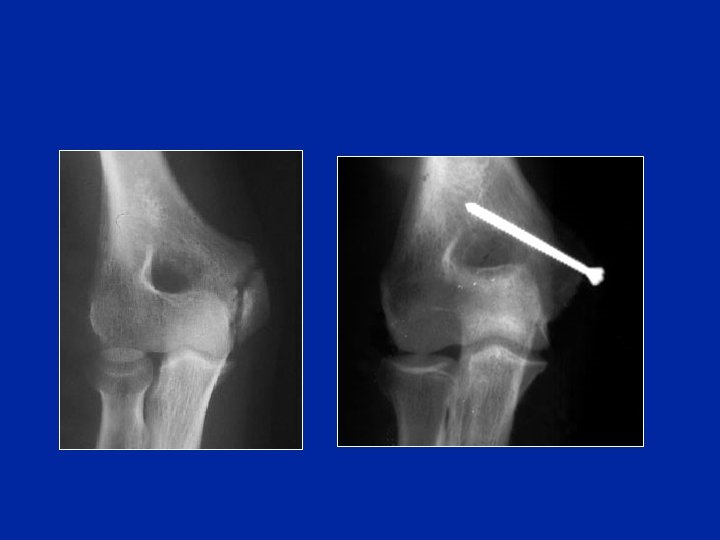

Condilo esterno

Fratture del condilo esterno

(fr di Kocher)